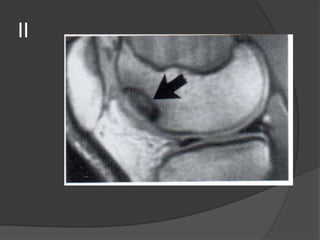

Grado 2

Grado II

• Roturas parciales

• Ligamento engrosado y áreas de hiperseñal en T1 y T2.

• Las fibras ligamentosas están separadas del hueso

cortical debido a la presencia de edema y hemorragia.